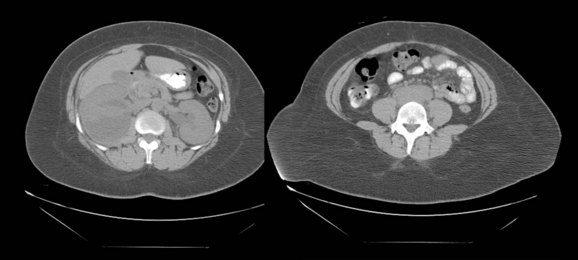

Before the advent of cross-sectional imaging, radiologic diagnosis relied upon imaging not the disease process itself but its secondary effects on the ureters. The classic radiologic findings included medial deviation of extrinsically compressed ureters with hydronephrosis. Medial deviation is a nonspecific finding, because it has been demonstrated in up to 18% of normal subjects (Saldino and Palubinskas, 1972). Hydronephrosis is typically demonstrated on ultrasonography, and there may also be a smooth, well-demarcated, hypoechoic or isoechoic mass anterior to the lumbar or sacral spine (Amis, 1991). Retrograde pyelography typically demonstrates hydronephrosis, with medially deviated and segmentally narrowed ureters without filling defects (Fig. 40–10). Currently, cross-sectional imaging with CT or MRI is the modality of choice for evaluating patients with suspected retroperitoneal fibrosis. Both modalities have been demonstrated to delineate accurately the extent of the disease when correlated with surgical exploration (Mulligan et al, 1989). CT typically reveals a well-demarcated retroperitoneal mass, isodense with muscle on unenhanced studies (Fig. 40–11) (Vivas et al, 2000). It typically surrounds the lower abdominal aorta, inferior vena cava, and iliac vessels—frequently enveloping the ureters. In contrast, masses secondary to malignancy usually displace the aorta anteriorly and the ureters laterally. Variable degrees of contrast enhancement may be seen, typically more pronounced earlier in the course of the disease when the presumably more-immature plaque has increased vascularity (Amis, 1991). Some have advocated noncontrast multidetector CT imaging combined with antegrade CT pyelography for evaluation, because it can define the fibrotic process and the level and degree of ureteral obstruction without administration of intravenous contrast material (Ghersin et al, 2004). However, the invasive nature of this diagnostic approach limits its applicability.

Figure 40–11 Unenhanced computed tomography performed in a patient with retroperitoneal fibrosis. Note hydronephrosis and soft tissue mass indistinguishable from the great vessels.

(Courtesy of Dr. Ronald Zagoria.)